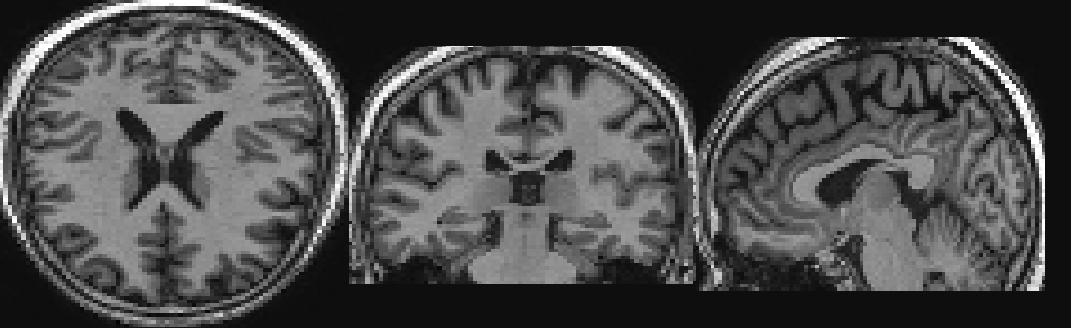

For our experiments we use MRI data made available as part of the Alzheimer’s Disease Neuroimaging Initiative (ADNI). ADNI is an ongoing, multicenter study designed to develop clinical, imaging, genetic, and biochemical biomarkers for the early detection and tracking of Alzheimer’s disease. The ADNI study began in 2004 and is now in its third phase. The dataset used here was originally prepared and analysed in [5] and consists of 755 patients in each one of the three classes (AD, MCI, HC), for a total of 2,265 scans. Statistical Parametric Mapping (SPM) was used to normalize the image data into an International Consortium for Brain Mapping template. The configuration includes a positron density template with no weighting image, and a 7th-order B-spline for interpolation whilst the remaining parameters were set to their default. We also normalised the data by subtracting the mean and dividing by the standard deviation. The dimension of each image is 68×95×7968957968\times 95\times 79, which results in 510,340 voxels. Figure 1 shows an example of three two-dimensional slices extracted from an MRI scan.

Refer to caption

Figure 1: Slices of an MRI scan of an AD patient, from left to right: in axial view, coronal view and sagittal view.